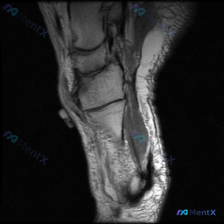

看到这个病例挺有意思,整理了完整资料和分析思路给大家参考 病例影像基础信息 这是一份足踝部矢状位T2加权MRI图像,覆盖后足区域(跟骨、距骨、距下关节、跟腱附着区),具体影像发现如下: 1. 骨骼信号:跟骨后部及体部可见广泛弥漫混杂T2高信号,提示骨髓水肿/充血/炎症;距骨体后部也可见边界模糊的信号...